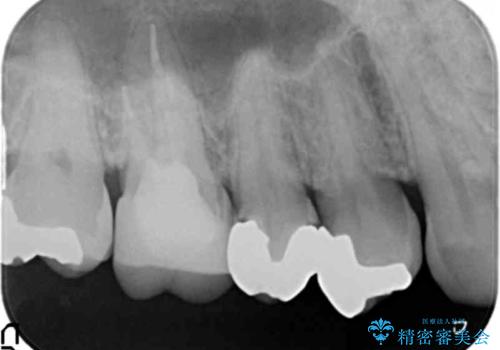

銀歯の下が虫歯 セラミックインレーに

- 銀歯の下が虫歯になっていたため、虫歯を取り、セラミックインレーで修復しました。

見るだけでは、わかりにくいのでしっかりレントゲンを診てもらえるような定期検診が大事です。

銀歯が合っていないなどは、見た目だけではわかりにくいことがあります。

早めに見つけて、症状が出る前に治すことが大事です。

歯科医師にレントゲンをしっかり診てもらうことが重要です。